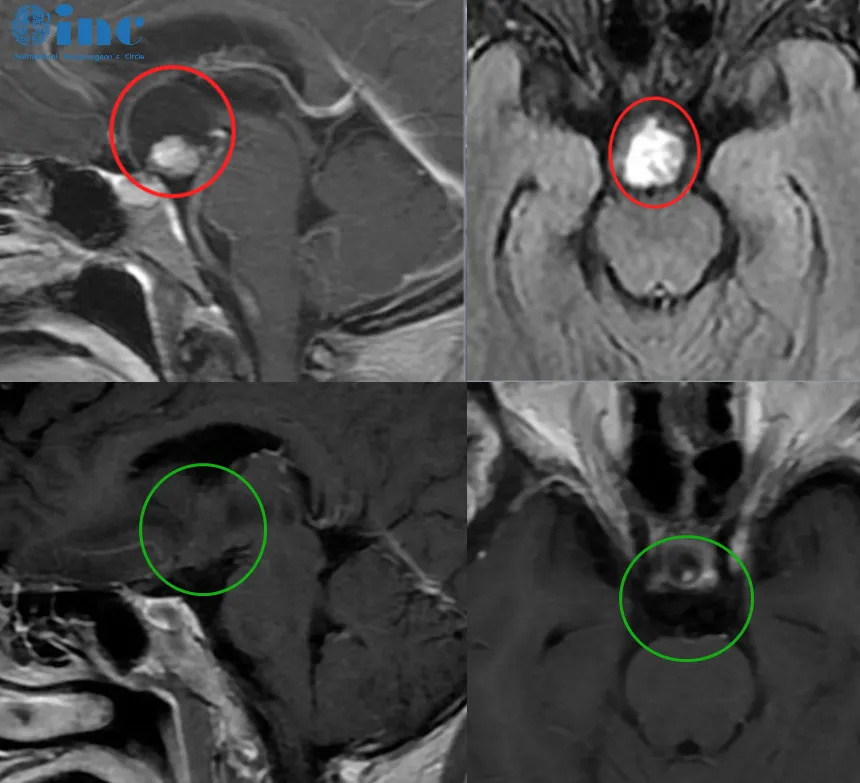

颅咽管瘤图片